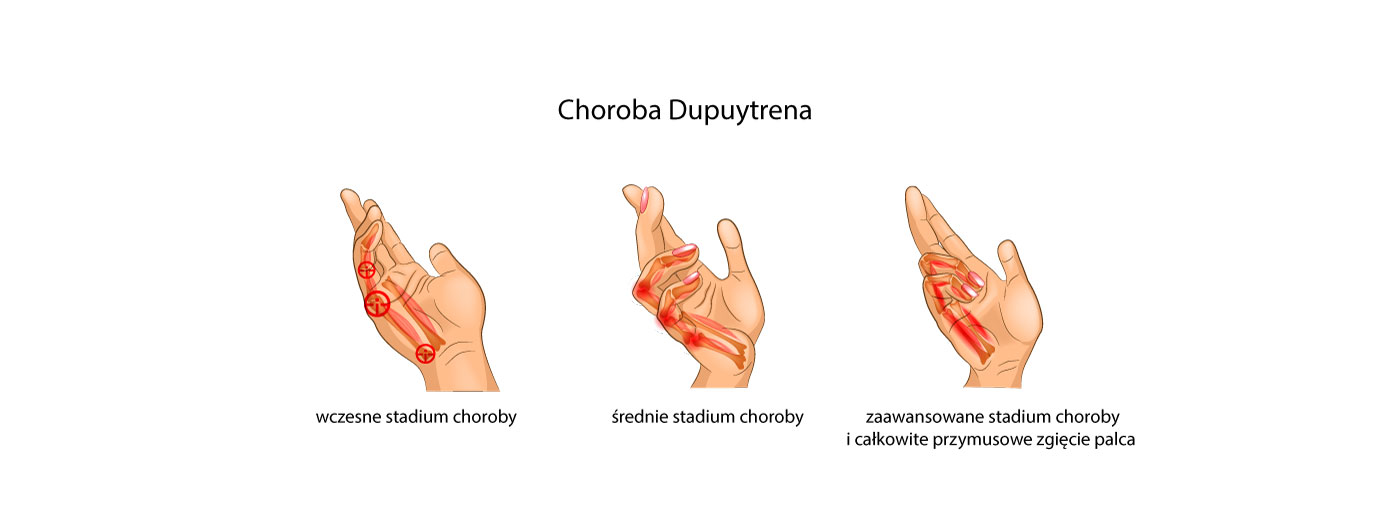

Choroba Dupuytrena to deformacja stawów ręki niewiadomego pochodzenia, która rozwija się latami. Może być dziedziczna. Polega ona na tworzących się pod skórą, na skutek stanów zapalnych, zgrubień i zwłóknień tkanek miękkich, które z czasem powodują przymusowe ustawienie palców dłoni w pozycji zgięciowej. Takie przymusowe zgięcie palców ręki i brak możliwości ich wyprostowania powoduje unieruchomienie dłoni i brak umiejętność wykonywania czynności dnia codziennego tj. ubieranie, mycie czy gotowanie. W przypadku zaawansowanego stadium choroby najczęstszą formą leczenia jest zabieg chirurgiczny, polegający na usunięciu tkanki powodującej przykurcz. Niestety, schorzenie ma charakter przewlekły i zgrubienia tkanek często powracają. Dlatego, dobrym sposobem na pasywne rozciąganie tkanek i zapobieganie ich przykurczom jest nasza szynowa orteza palców OKG-14.